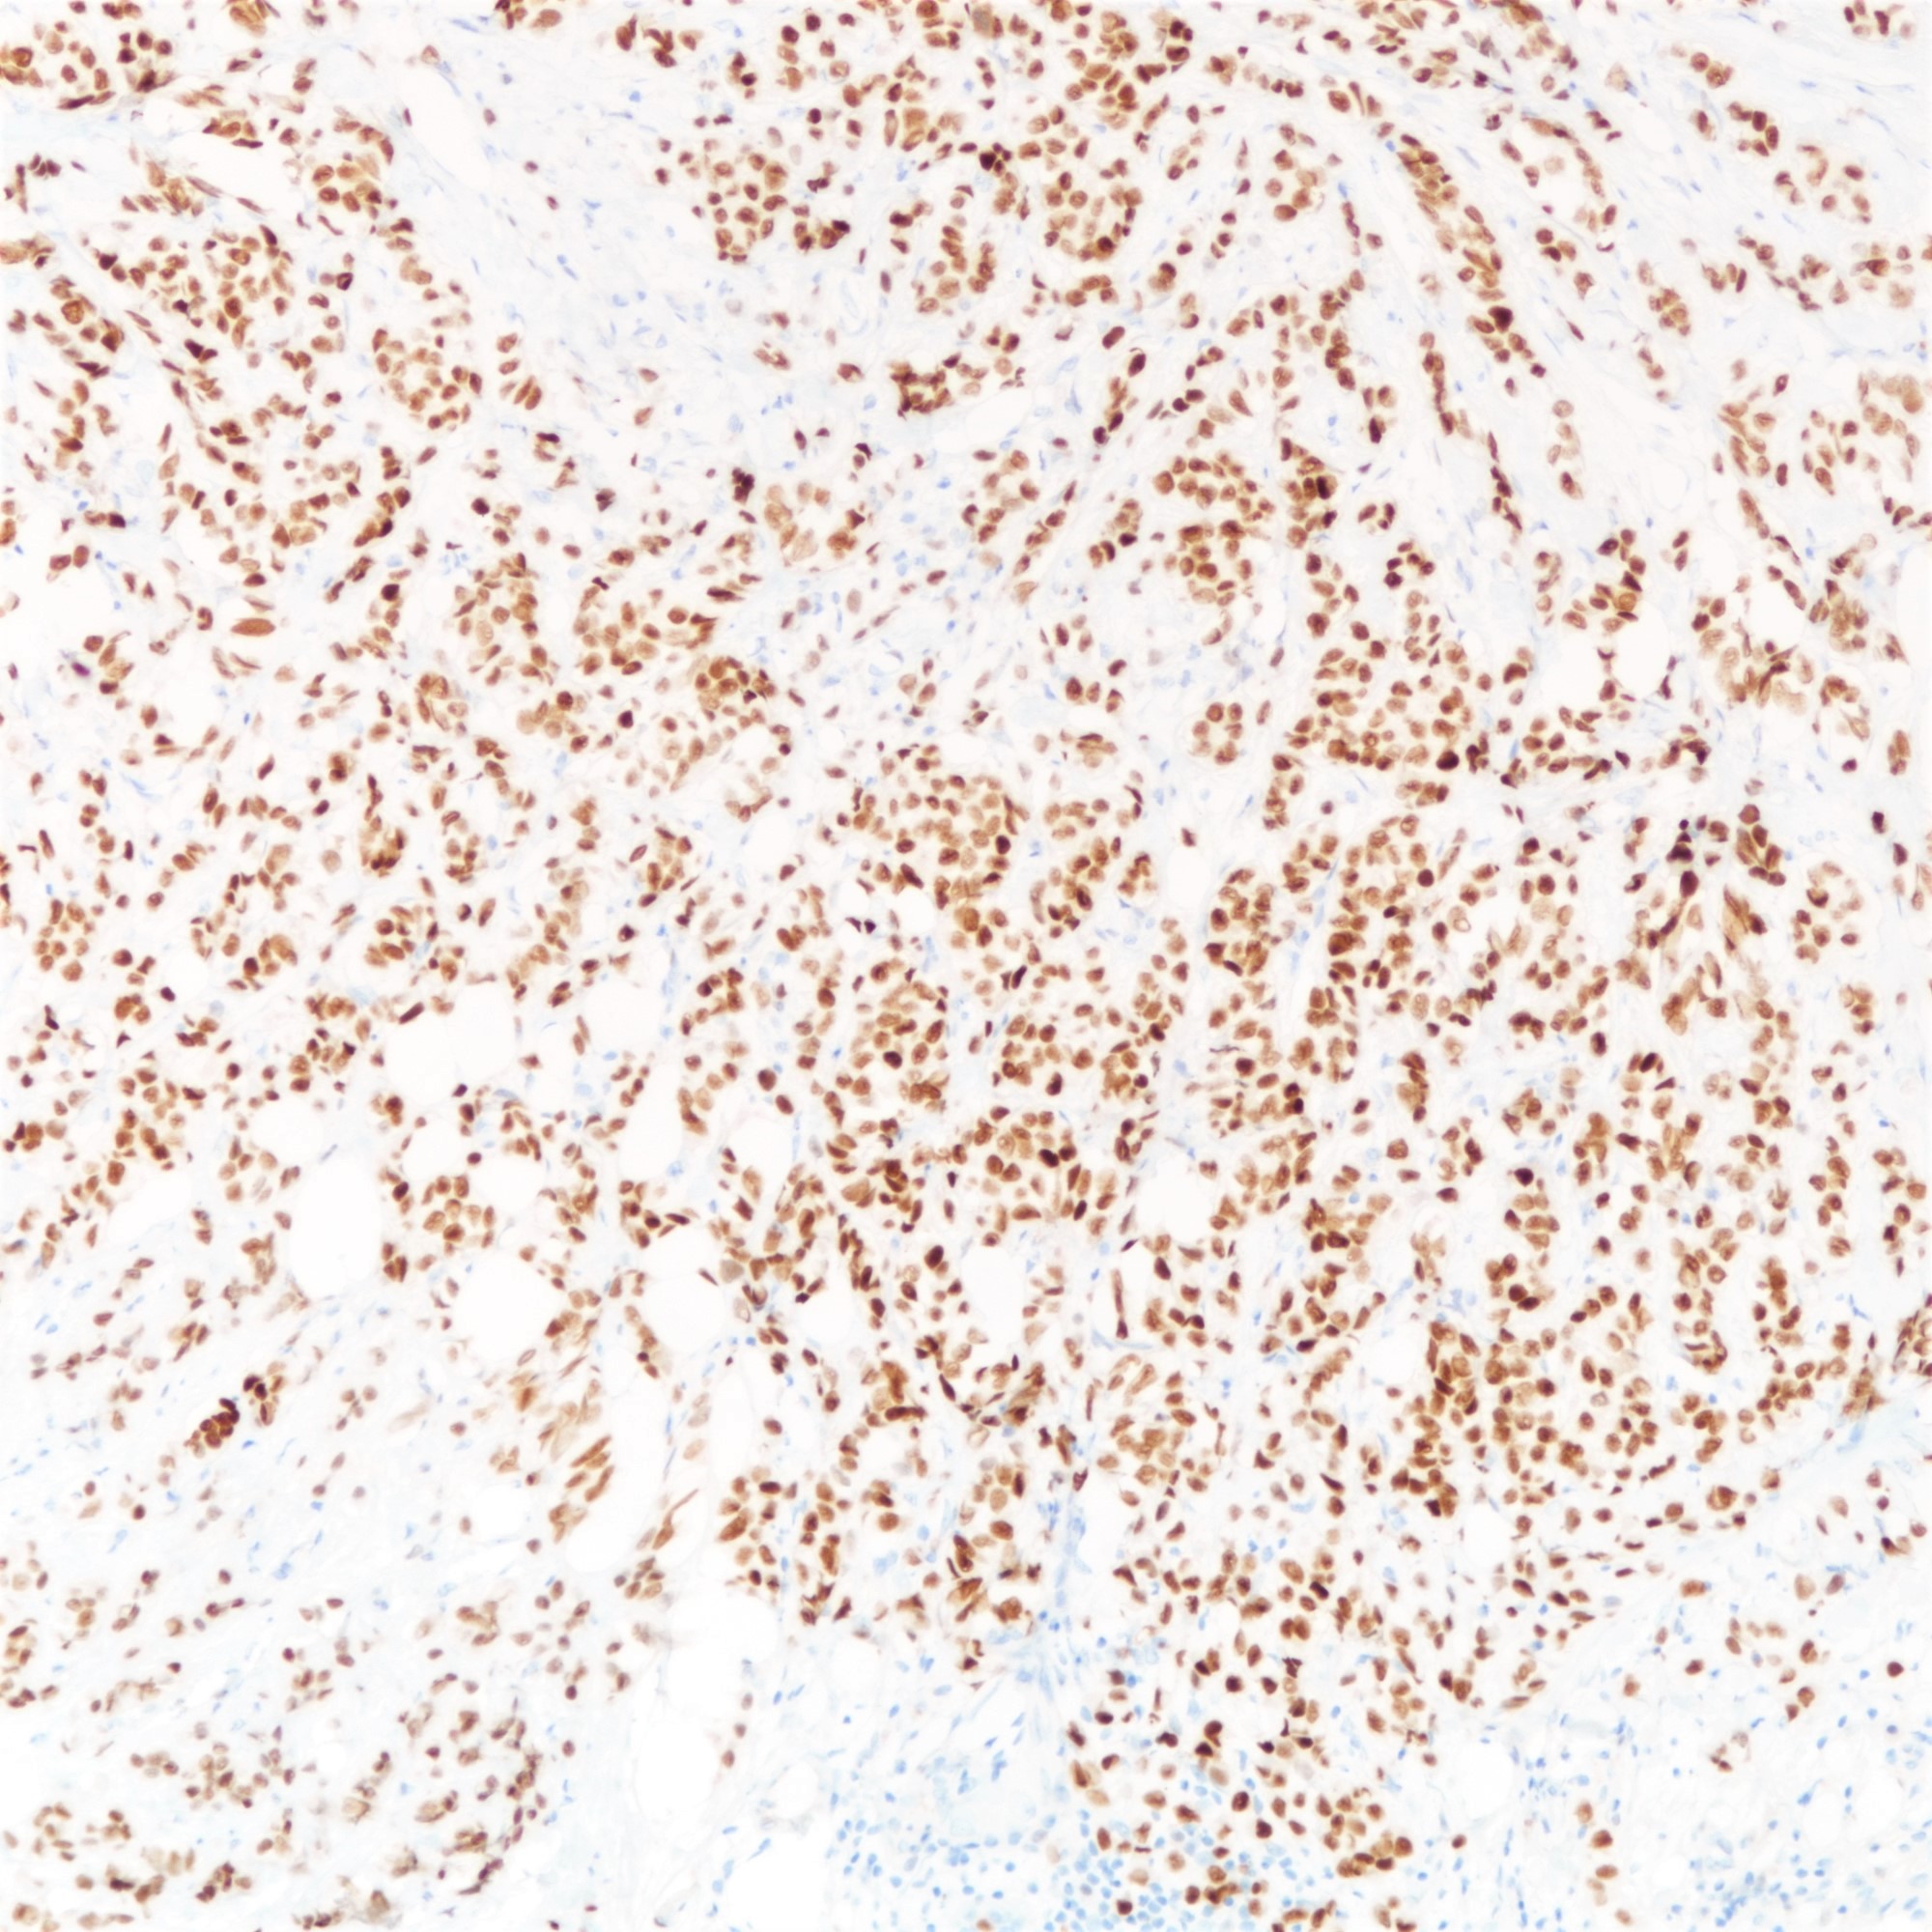

Positive stains

- Estrogen receptor (97%) and progesterone receptor (80%) (Breast Cancer Res Treat 2012;133:713)

- Androgen receptor (87%) (Virchows Arch 2005;447:695)

- GATA3 (97 - 100%) (Am J Surg Pathol 2013;37:1756, Ann Diagn Pathol 2015;19:6)

- Mammaglobin (69%) (Ann Diagn Pathol 2015;19:6)

- GCDFP-15 (52%) (BMC Cancer 2014;14:546)

- Mucicarmine (highlights intracellular mucin)

- Comment: Sections show breast tissue with malignant cells in a diffuse and discohesive pattern, with some forming single files and small clusters. Targetoid pattern is noted. The tumor cells show mild nuclear pleomorphism with rare mitoses, corresponding to a Nottingham histological grade of I. No lymphovascular permeation is seen. The tumor measures ___cm in maximal dimension. The remaining breast tissue and nipple are unremarkable. All the resection margins are clear, with a minimal clearance of ___cm at the ___ margin. Immunohistochemical staining shows tumor cells are E-cadherin negative. The features are those of an infiltrating lobular carcinoma, classic type.